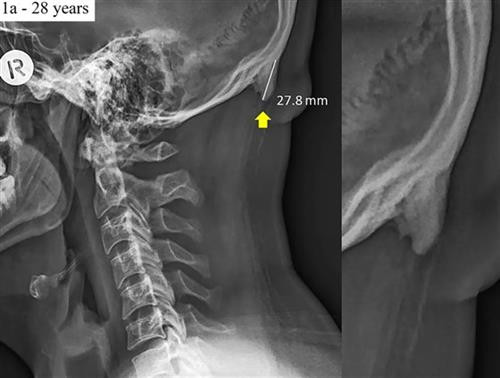

| ស្នែងលៀនចេញពីលលាដ៍ក្បាលខាងក្រោយរបស់បុរសម្នាក់អាយុ ២៨ ឆ្នាំ។ រូបថត៖ BBC |

១. ពកឆ្អឹងលលាដ៏ក្បាលដូចដុះស្នែង

ក្រុមអ្នកស្រាវជ្រាវដែលសិក្សាអំពីកាំរស្មីអ៊ិចលើមនុស្សពេញវ័យចំនួន ១.២០០ នាក់ដែលមានអាយុ ១៨ ដល់ ៣០ ឆ្នាំ បានរកឃើញទម្រង់ឆ្អឹងដូចទម្ពក់ ឬស្នែងលៀនចេញពីលលាដ៍ក្បាលខាងក្រោយនៃក្រុមមនុស្សទាំងនេះចំនួន ២/៣។

ក្រុមអ្នកស្រាវជ្រាវសន្និដ្ឋានថា ការលេចរូបរាងឆ្អឹងបែបនេះឡើងក្នុងចំណោមមនុស្សក្មេងៗ ប្រហែលបង្កឡើងដោយសារឱនក្បាលឈ្ងោកទៅមុខពេកនៅពេលប្រើស្មាតហ្វូន ឬឧបករណ៍កាន់នឹងដៃផ្សេងទៀត។

សកម្មភាពនេះបានផ្លាស់ប្តូរទម្ងន់ពីឆ្អឹងខ្នងទៅសាច់ដុំនៅផ្នែកខាងក្រោយនៃលលាដ៍ក្បាលដោយបង្កឱ្យមានការលូតលាស់ឆ្អឹងនៅក្នុងសរសៃពួរនិងសរសៃចង។